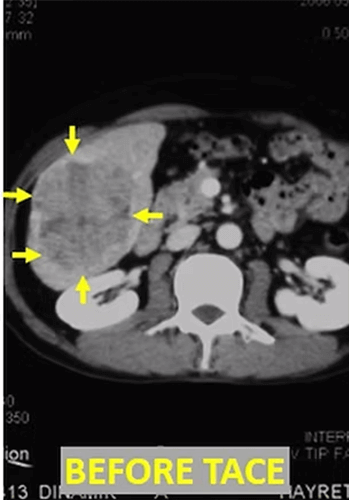

In our patient who has a large (10cm) HCC (arrows) in the liver, the control computed tomography after Lipiodol-TACE shows that the tumor has lost its viability and its diameter decreased to 4 cm.